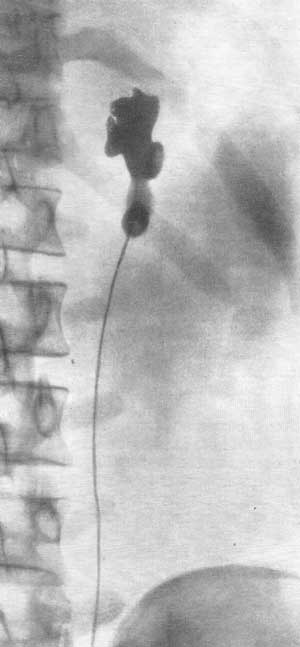

Первые проявления заболевания можно выявить при помощи ультразвуковой диагностики. Патология почек у плода нередко определяется уже при проведении скрининговых УЗИ у беременных. Чаще всего в почках образуются кисты, иногда множественные (поликистоз почек), сами органы уменьшены в размерах и могут срастаться между собой (такое явление носит название подковообразной почки). При гломеруоцитозе почек гипопластического типа также может определяться аномальное расположение сосудов органов и их разветвление. Нередко обнаруживается необычная локализация мочеточника. При УЗИ малого таза у женщин с гломеруоцитозом почек гипопластического типа часто выявляются пороки развития репродуктивной системы (двурогая или рудиментарная матка). УЗИ печени свидетельствует об аномальном строении органа (изменении его формы и размеров).